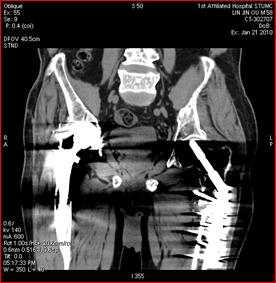

高能量X射线可以去除高密度金属引起的伪影

常规CT 宝石能谱CT

140keV能量成像可以除去金属引起的伪影,更加清晰观察术后情况